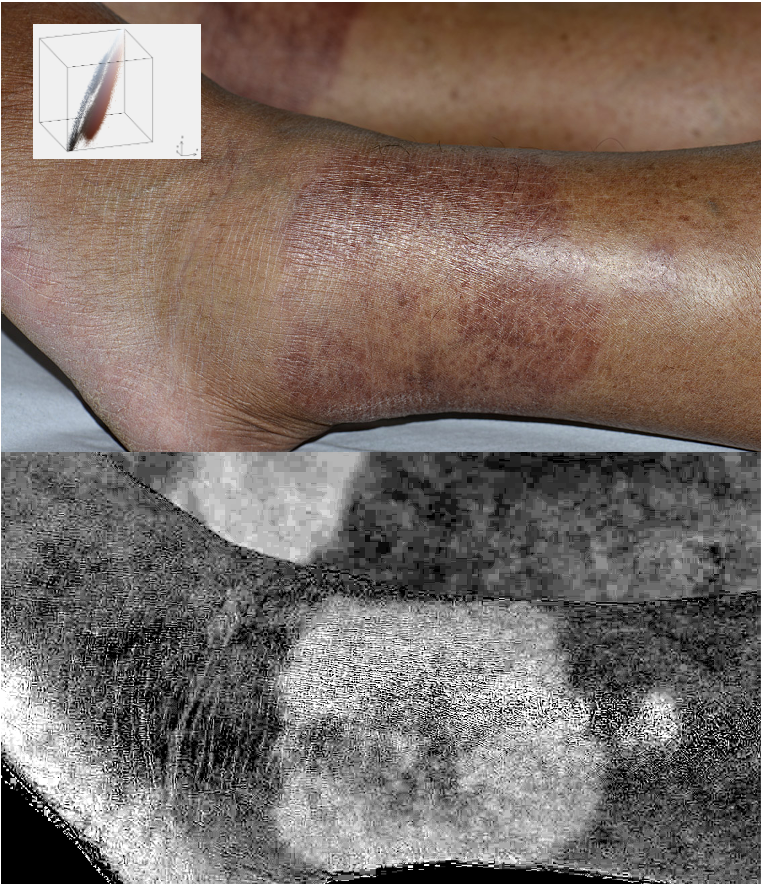

Processed and unprocessed images of skin displayed side-by-side

Current ongoing areas of research include improving visualization and quantification of cutaneous structures and dynamics (e.g. veins, erythema, topical medications, cutaneous microvasculature) by a combination of computational and optical approaches, fractionated cryotherapy for skin resurfacing, and new approaches to the treatment of photosensitive disorders.